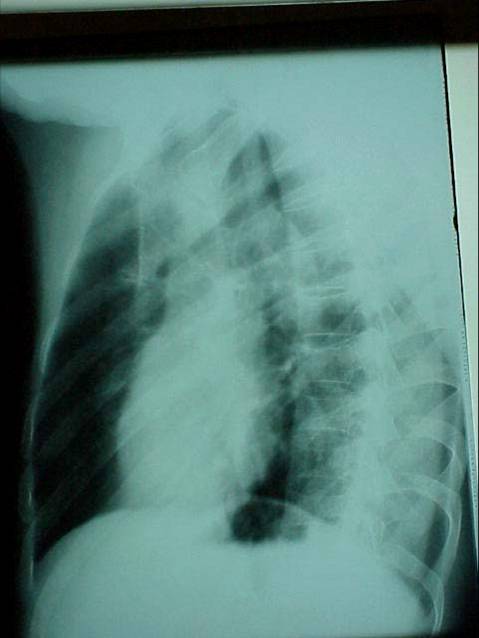

照片名称:右肺炎